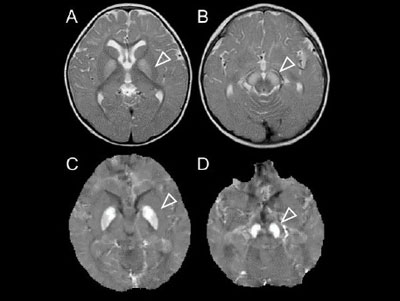

画像はリリースより

研究グループは、同院小児神経科に通院中の患児で、幼児期に発熱に伴い痙攣重積、痙攣群発をきたした3例において、痙攣後に頭部MRI画像を撮像。その結果、頭部MRI画像に淡蒼球、黒質の対称性の腫大、高信号を一過性に認めたという。頭部MRI画像のほか、ウイルス検査、細菌培養検査、乳酸、ピルビン酸や代謝異常といった種々の検査を行ったが、いずれの検査においても異常所見を認めなかったことから、神経疾患の可能性を疑い、次世代シークエンス解析を実施。その結果、NBIAの一型であるSENDA/BPANの原因遺伝子WDR45変異を同定したという。さらに、MRIで定量的な磁化率の解析である定量的磁化率マッピングQSM解析を行ったところ、淡蒼球、黒質への鉄沈着が確認され、SENDA/BPANの診断に矛盾がないことを証明したとしている。

以上の研究結果より、SENDA/BPANの小児期の特徴的なMRI画像所見として、発熱に伴う痙攣重積・群発後に一過性の淡蒼球、黒質に高信号があることが明らかになった。小児期には、普段はMRI画像で確認できるような淡蒼球、黒質の所見が確認できないものの、発熱時の痙攣重積・群発時には不耐が生じ浮腫像を呈したことが示唆され、同例の病態に関連している可能性が示されたという。今回の結果は、小児期の診断の新たな一助になりえることに加え、SENDA/BPANの新たな病態解明につながることが期待されると研究グループは述べている。